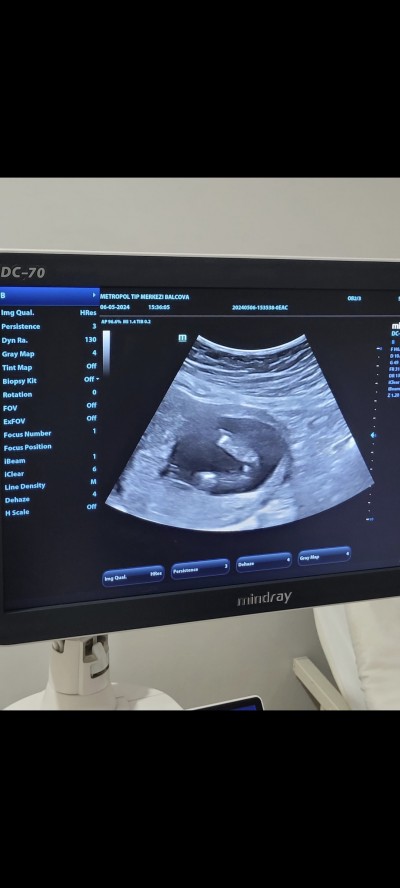

Cinsiyet tahmini yapabilirmisiniz

Gebelik haftası 15+5

Şişkinlik erkek gibi duruyor ama haftaya baktım olduğun haftada pipisinin çok jet gözükmesi lazımdı onun için kız da olabilir

Doktor bir tahminde bulunmadı mı bence bacak arası boş duruyor.

%70kiz dedi net birşey söylemedi

Benim de 14 haftalıkenken yüzde 60 kız demişti daha sonra 16 haftalık kontole gitigimde  erkek dedi , ama benimki bacak arasında Kordon vardı .ondan yanılmışti